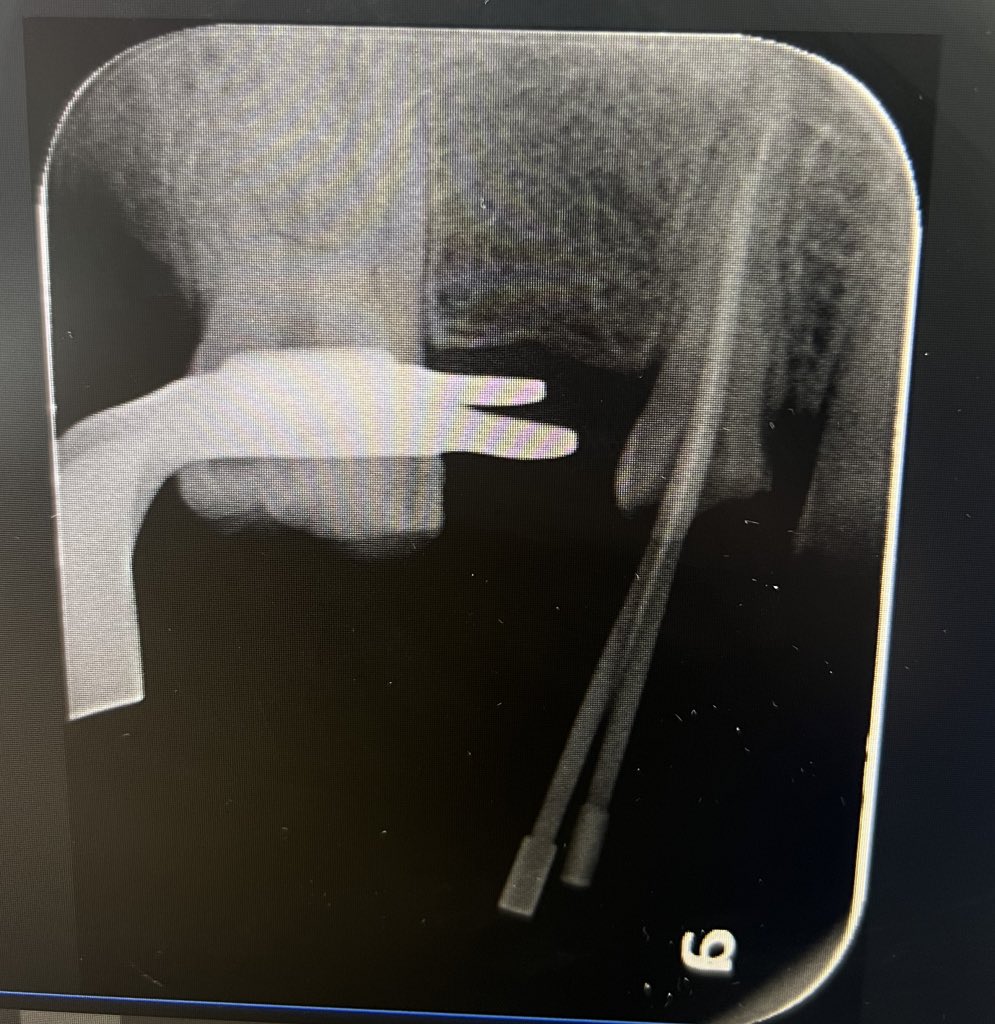

Today’s case:

Rct of #11 Dx : PI/AAA

• 1st visit: Open access, irrigation, abscess drainage, and dressing the canal with Ca(OH)₂.

• 2nd visit (after 30 days): Reopening the tooth, irrigation performed; the canal was completely dry and ready for obturation.

Patient is fine😁